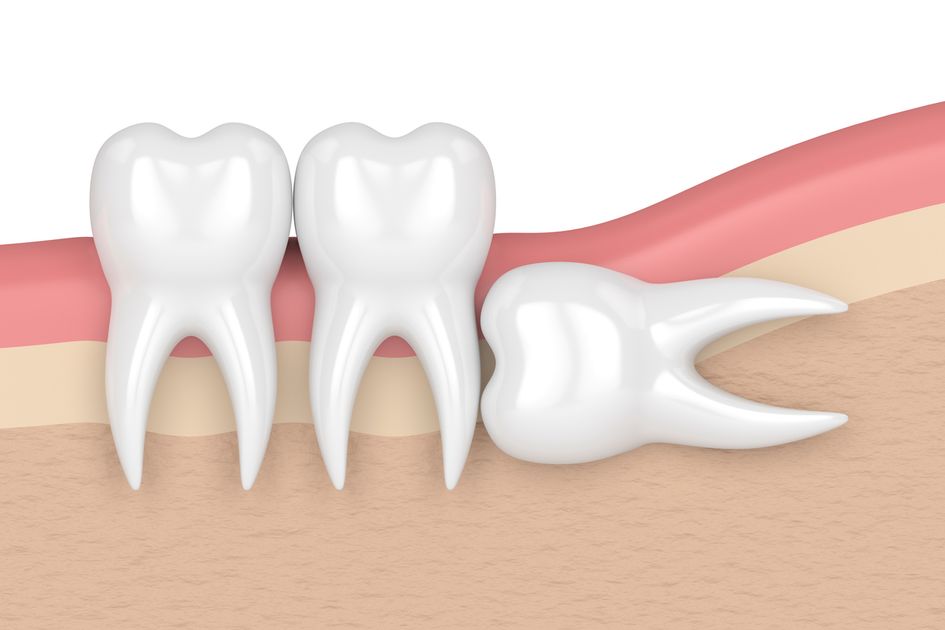

Secara anatomi, pertumbuhan gigi memerlukan ruang yang cukup pada rahang. Ketika ruang tersebut tidak tersedia atau arah pertumbuhan gigi tidak ideal, gigi akan terjebak di dalam gusi atau tulang rahang. Kondisi inilah yang disebut sebagai impaksi. Impaksi dapat bersifat parsial, ketika sebagian gigi masih terlihat di permukaan gusi, atau total, ketika gigi sama sekali tidak muncul.

Dalam praktik kedokteran gigi, impaksi gigi diklasifikasikan berdasarkan posisi dan arah pertumbuhan gigi yang terhambat. Klasifikasi ini membantu dokter gigi menentukan pendekatan perawatan yang paling tepat bagi setiap pasien. Secara umum, ImpaksiGigi dapat dibedakan menjadi impaksi vertikal, horizontal, mesioangular, dan distoangular.

Impaksi vertikal terjadi ketika gigi tumbuh lurus tetapi tidak memiliki cukup ruang untuk muncul sepenuhnya. Impaksi horizontal ditandai dengan posisi gigi yang tumbuh mendatar dan menekan akar gigi di depannya. Sementara itu, impaksi mesioangular merupakan kondisi paling umum, di mana gigi tumbuh miring ke arah depan rahang. Impaksi distoangular lebih jarang terjadi dan ditandai dengan arah pertumbuhan gigi yang miring ke belakang.

Selain berdasarkan arah pertumbuhan, ImpaksiGigi juga dibedakan berdasarkan kedalamannya di dalam tulang rahang. Gigi yang terletak dangkal relatif lebih mudah ditangani dibandingkan gigi yang tertanam jauh di dalam tulang. Pemeriksaan radiologi, seperti foto rontgen panoramik, menjadi alat penting untuk menilai tingkat keparahan impaksi.